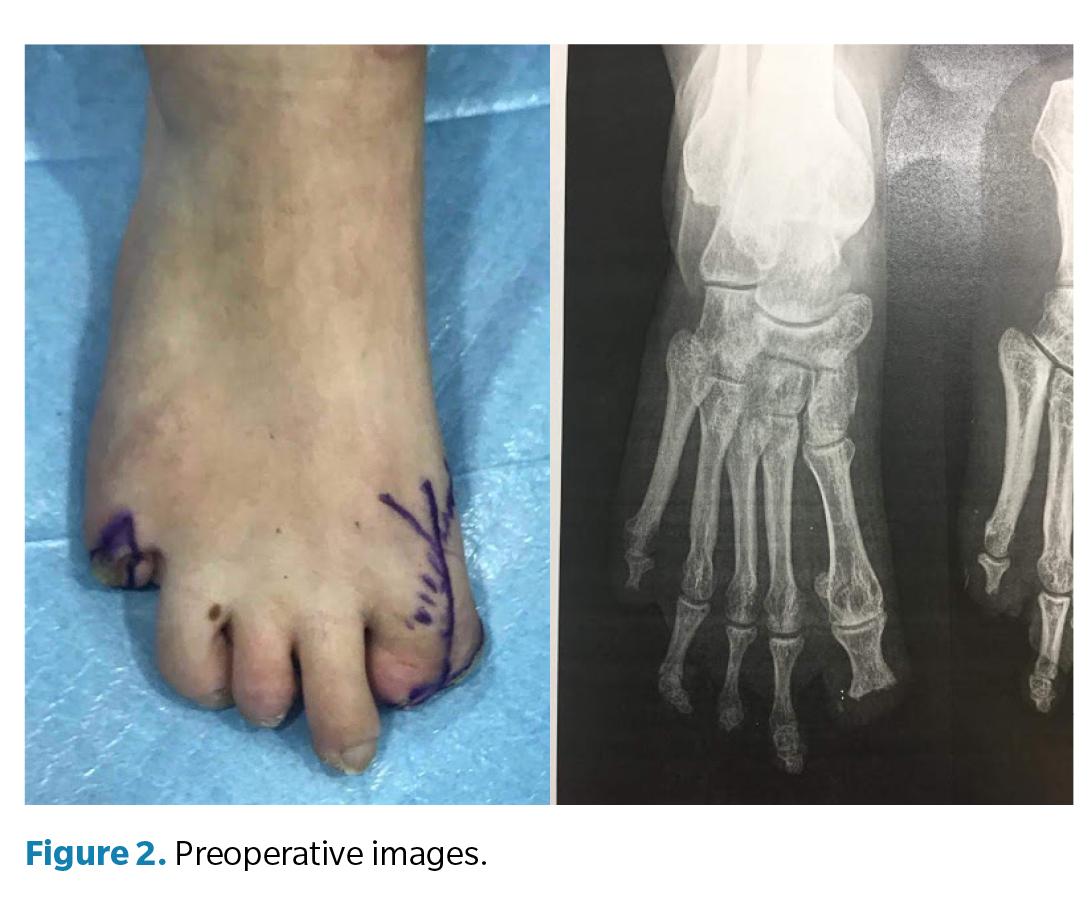

Clinical examination (Figure 2) of the right foot revealed a rigid first metatarsophalangeal joint, with the hallux in fixed plantar flexion and absence of the distal phalanx, producing a painful stump and altered propulsion during gait. The deformity was interpreted as a result of postamputation shortening and cicatricial fibrosis of the residual flexor, with no distal traction. Direct pressure elicited pain over the residual tip of the first toe, which was deformed but retained limited joint mobility. The right fifth toe had a painful hypertrophic scar with a residual corn secondary to total amputation. The left foot showed normotrophic scars at the partial amputation sites of the second and third toes, with no pain or plantar overload, thus requiring no surgery.